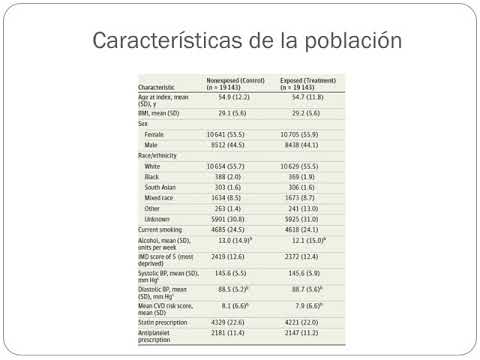

Asociación entre adherencia a estatinas y mortalidad en pacientes con enfermedad cardiovascular. Dr. Julián Colla. Residencia de Cardiología. Hospital C. Argerich. Buenos Aires